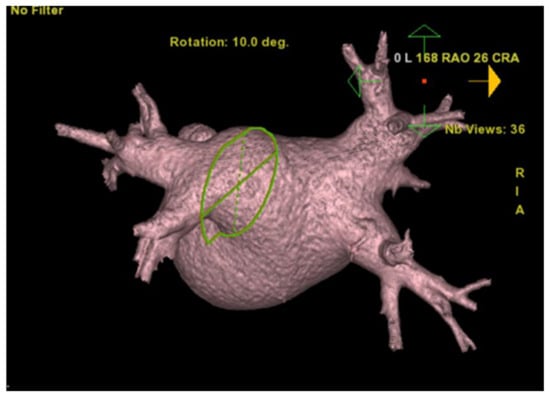

5. Computed Tomography (CT)

Cardiac computed tomography uses multiple X-ray beams emitted by a CT scanner rotating at very high speed and various angles in order to create cross-sectional images. The X-ray beams travel through the body, and they are collected by a detector array that can generate an image. Depending on the path of the beam through tissues of varying densities, a greyscale signal is created. Bone appears white (hyper-dense); the air is black (hypo-dense), blood and muscle are various shades of grey (Figure 11). Contrast is often used in order to enhance differentiation between tissues [21,22]. Coronary angiography also makes use of X-rays in order to visualize the heart vasculature without the need for invasive coronary catheterization. Via software post-analysis we can produce a three-dimensional image of heart vessels and evaluate atherosclerotic and stenotic lesions (Figure 12 and Figure 13). With computed tomography we can also visualize the accumulated calcium that is concentrated in different cardiac structures, such as the mitral annulus and leaflets, aortic cusps, pericardium, and coronary arteries, and quantify it via Agaston units or calcium score. For example, in aortic stenosis with the use of established thresholds of calcium score, we can differentiate between severe forms of the disease in special cases and choose the appropriate treatment for them [23,24]. Additionally, we can calculate the coronary calcium score (CAC), which according to the latest US and European guidelines can be used as a risk modifier in atherosclerotic coronary artery disease with incremental value in primary prevention [25,26,27].

Figure 12. Computed tomography: 3-D reconstruction of the left atrium along with the four pulmonary veins.

Figure 13. Computed tomography: 3-D reconstruction of the ascending aorta along with the three coronary arteries: left anterior descending (LAD), left marginal branch (LMB).